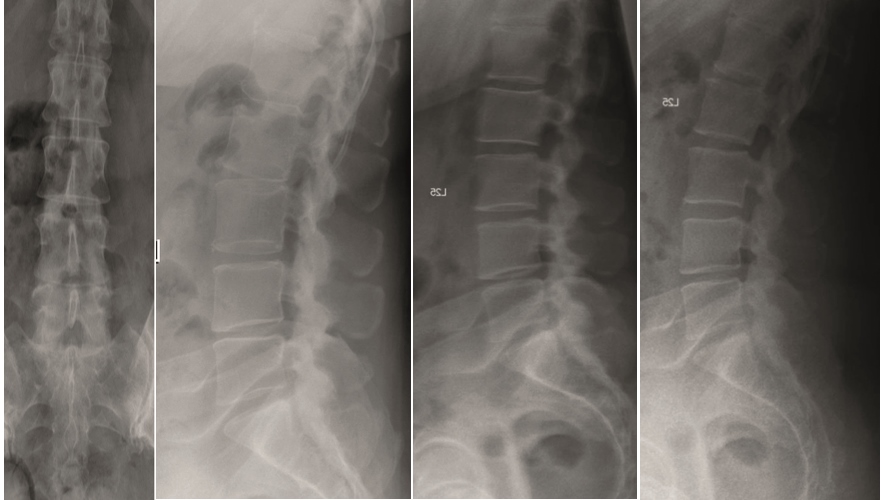

Multilevel facet pathology is shown in Fig 6. Intraoperative and postoperative images are shown (Fig 7-9).

A 40-year-old man 5 years after ALIF L4-L5 using SynFix with axial low back pain. The CT scan shows locked pseudarthrosis (Fig 17). Nonoperative treatment failed. The treatment option was bilateral Facet Wedge at L4-L5.

A less invasive approach was used with Insight Retractor using the bilateral Facet Wedge. No bone graft. X-ray follow-up after 3 months and CT assessment after 6 months (Fig 18-19).